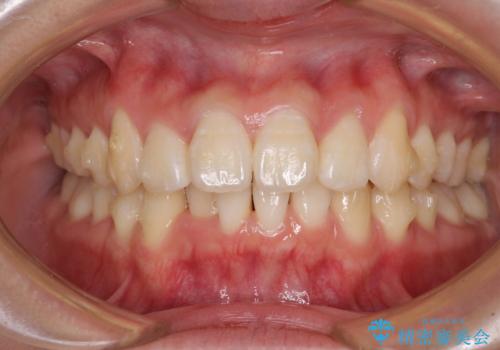

上下前歯の叢生をインビザラインできれいに

- 前歯のデコボコを気にして来院された患者様です。

前歯が重なっていることで口元が閉じにくくなっていたため、歯列全体の側方への拡大と、歯と歯の間を少し削ってスペースを獲得することとしました。